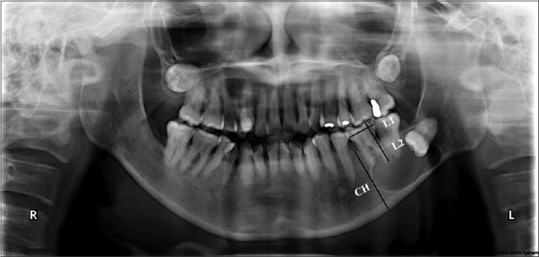

Materials and methods: Data were analysed from 40 cases, including 31 cases of odontogenic cyst and 9 cases of cyst-like tumour, treated at Chulalongkorn University's Faculty of Dentistry from 2009 to 2019. The percentage of cystic size reduction and percentage of change in radiographic density were analysed before the procedure and three months after treatment. The density and size of the odontogenic cysts were determined using Image J software version 1.43.